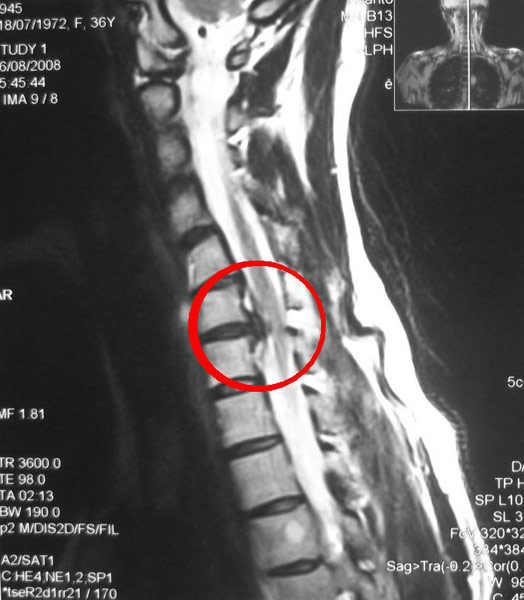

При различных патологиях позвоночника может возникнуть выпячивание грыжи. Это состояние создает давление на спинной мозг и раздражает нервные окончания, что приводит к дискомфорту и сильным болевым ощущениям.